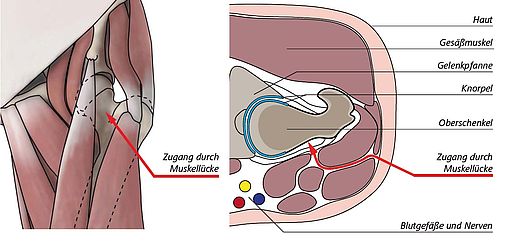

Der Patient wird in Seitenlage auf dem Operationstisch gelagert, die betroffene Seite zeigt zur Decke. Durch einen kurzen Hautschnitt von etwa 8 cm Länge wird die Muskellücke zwischen den vorderen und den hinteren Muskelgruppen aufgesucht. In dieser Muskellücke verlaufen keine großen Nerven oder Blutgefäße, so dass auf diese Weise die Gelenkkapsel gefahrlos erreicht werden kann. Der Raum über der Gelenkapsel wird mit zwei speziellen Haken aufgespreizt. Die Muskeln werden

zur Seite gehalten, nicht aber abgelöst oder durchtrennt. So öffnet sich dem Operateur ein Fenster. Es folgt dann die Längsspaltung der straffen Hüftbänder und eine teilweise Ablösung im Ansatzbereich. Zwei weitere Haken werden eingesetzt, so dass nun das Gelenk einsehbar ist. Über diesen Zugang erreicht man auf direktem Weg die Stelle, an der sich die schädigenden Formstörungen befinden.

Liegt ein Beißzangen-Phänomen vor, wird der Pfannenrand um wenige Millimeter verschmälert. In besonderen Fällen kann die Gelenklippe abgelöst, der knöcherne Pfannenrand reduziert und anschließend die Gelenklippe wieder angenäht werden.